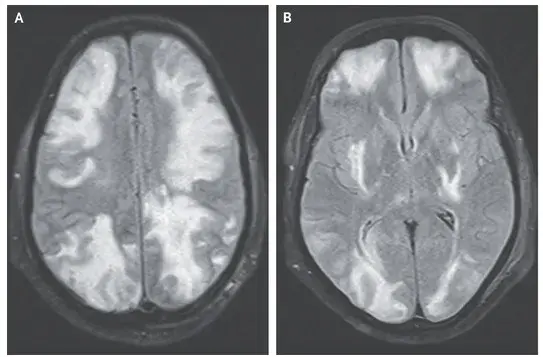

Nefropatía Membranosa: ¿Y si el paciente no responde al tratamiento inicial?

Nefropatía Membranosa: ¿Y si el paciente no responde al tratamiento inicial?

En este video, abordamos estrategias para tratar a pacientes con nefropatía membranosa que no responden al tratamiento inicial. Se enfatiza la importancia de la reevaluación constante y del ajuste del régimen de tratamiento en función de los resultados y del estado del paciente.

Cómo tratar la Nefropatía Membranosa de manera práctica

Cómo tratar la Nefropatía Membranosa de manera práctica